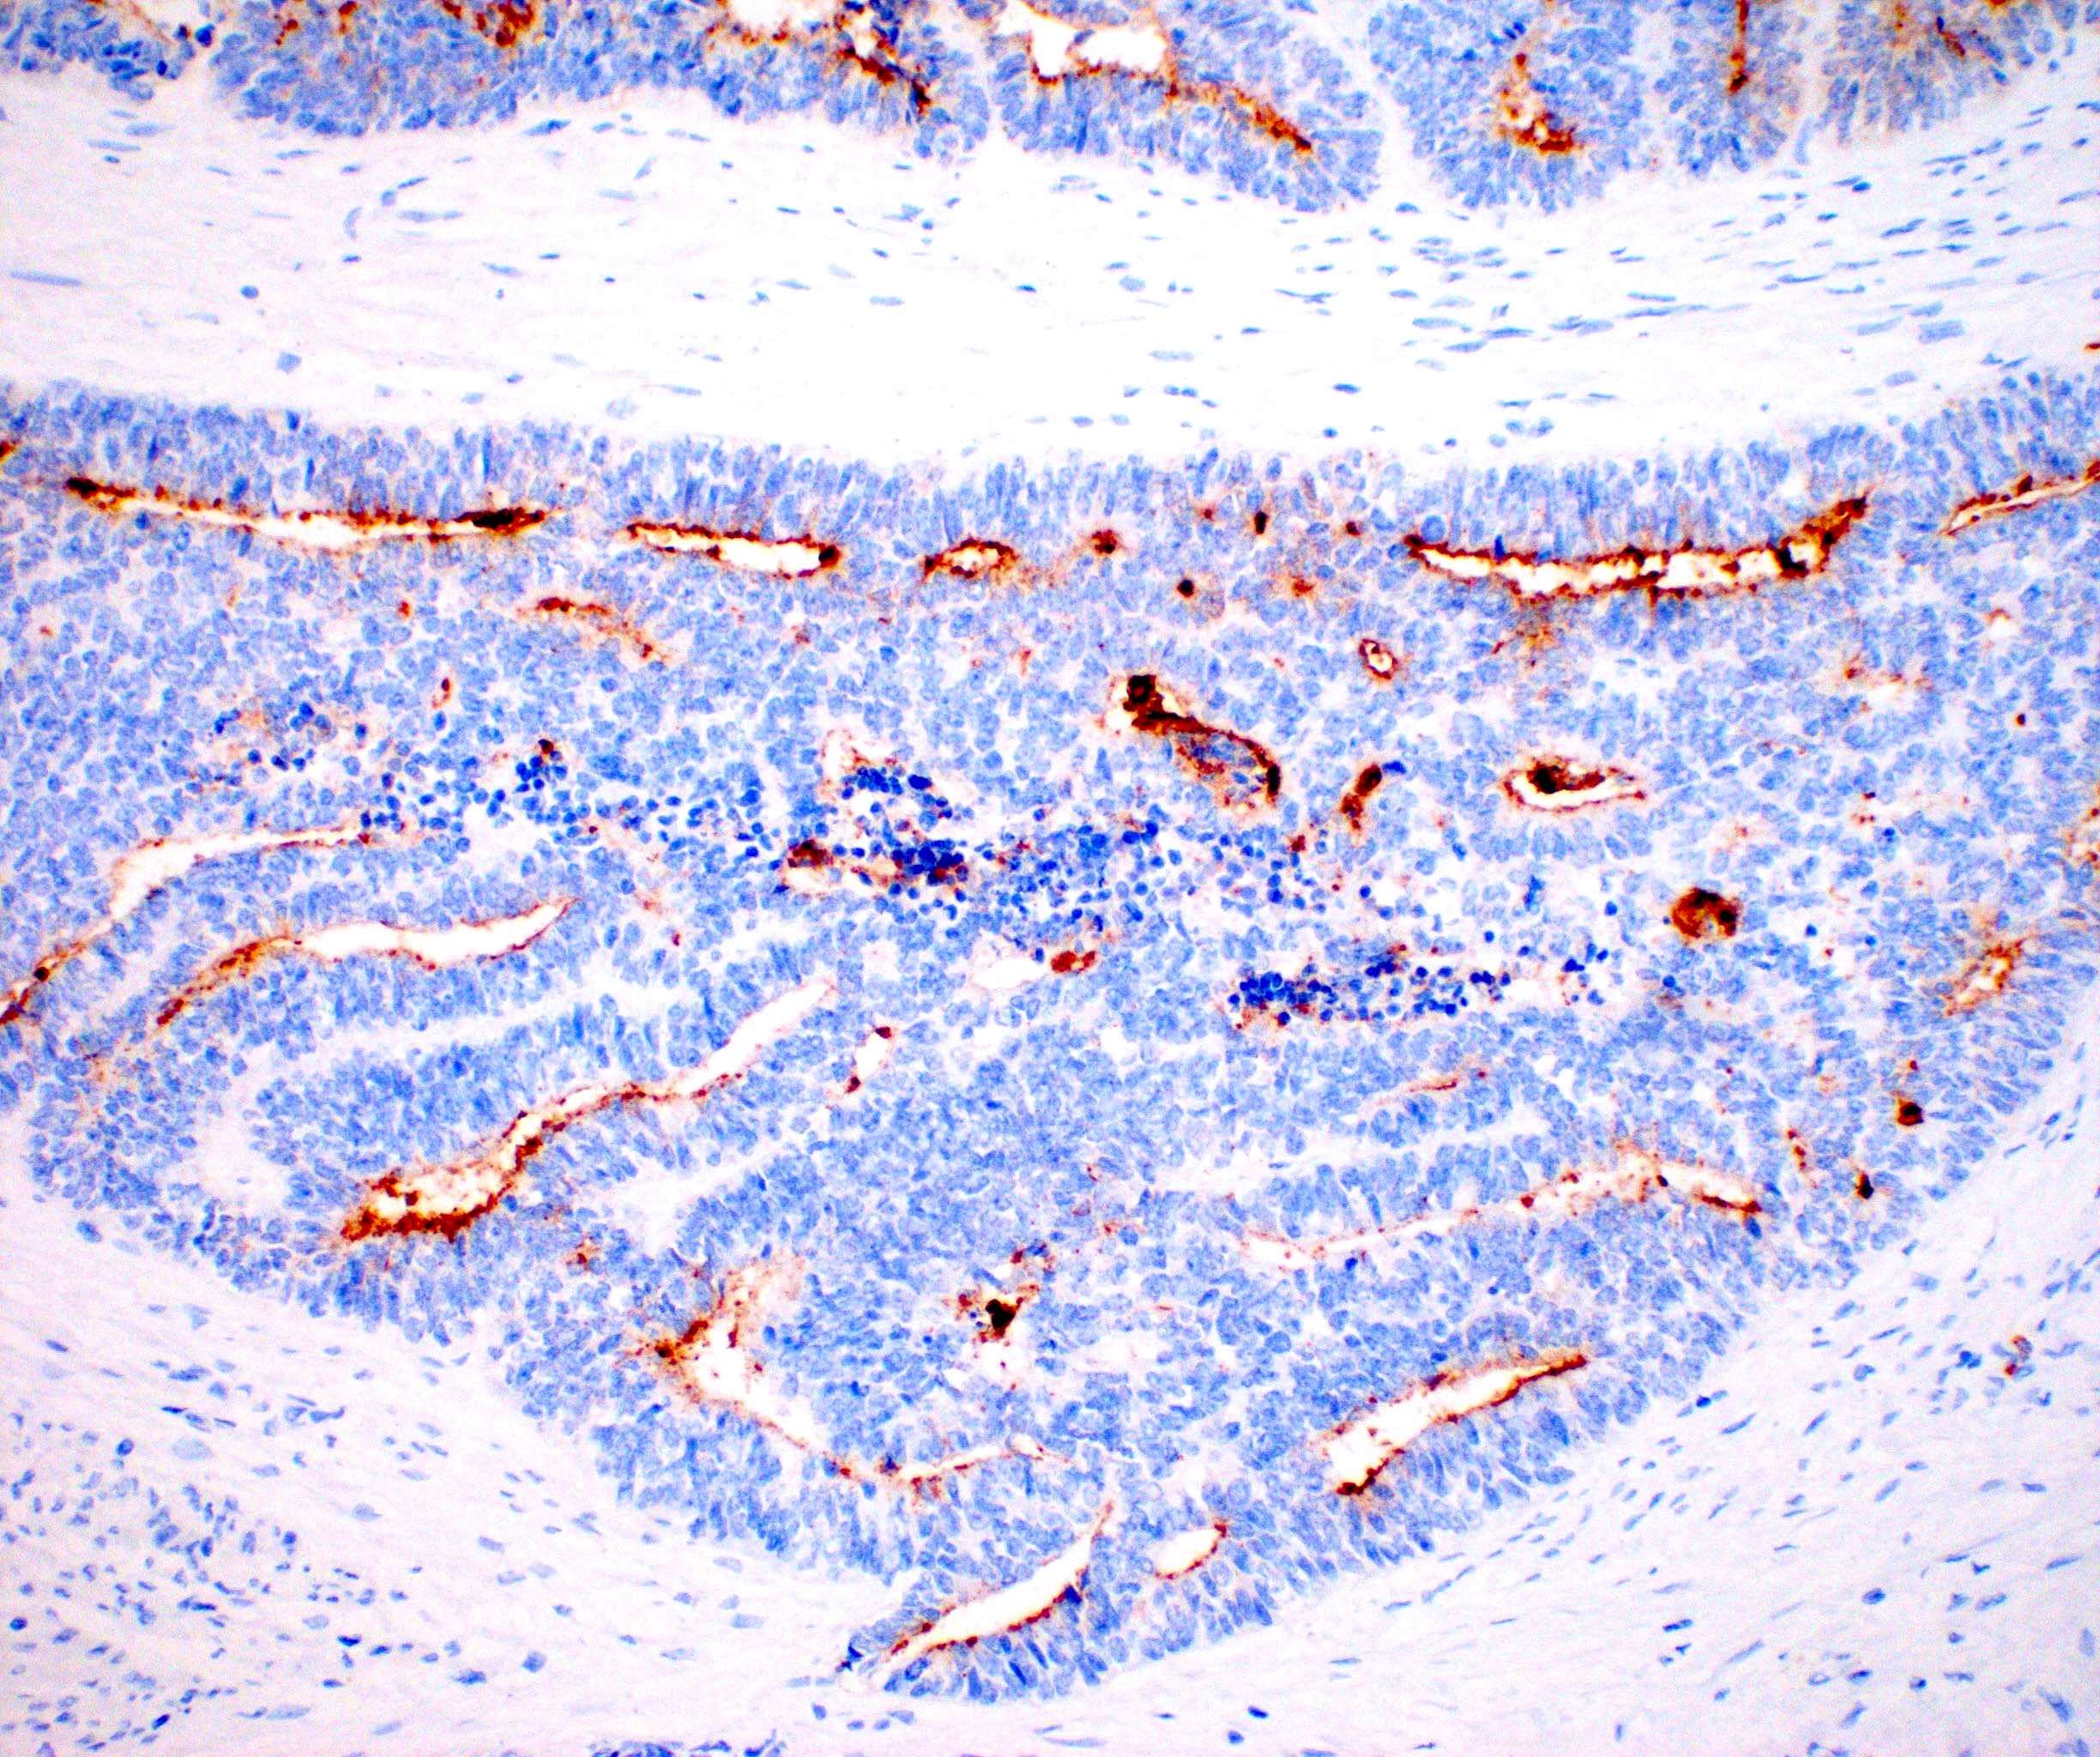

Microscopic (histologic) images

Contributed by Daniel Graham, M.D., Adele Wong, M.B., B.Ch., B.A.O. and Lucy Ma, M.D.